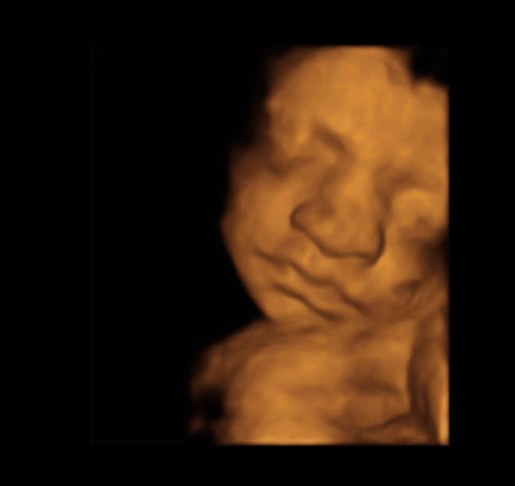

Ja det er helt vildt hvad man kan se...

Fik scanningen i julegave, så er super.

Er vildt at man kan se tydelige ansigtstræk. Er ikke i tvivl om hvem der er faren.